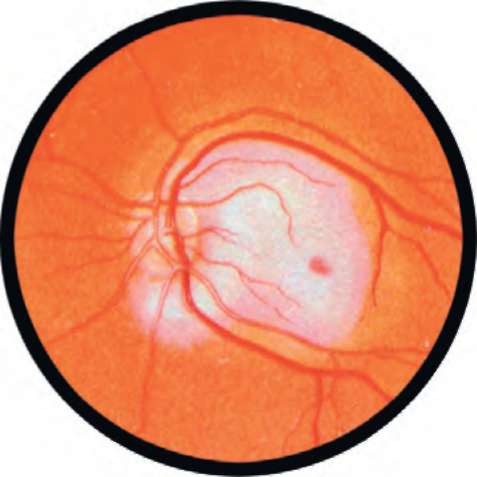

Рис. 23.1. Оптический неврит при рассеянном склерозе